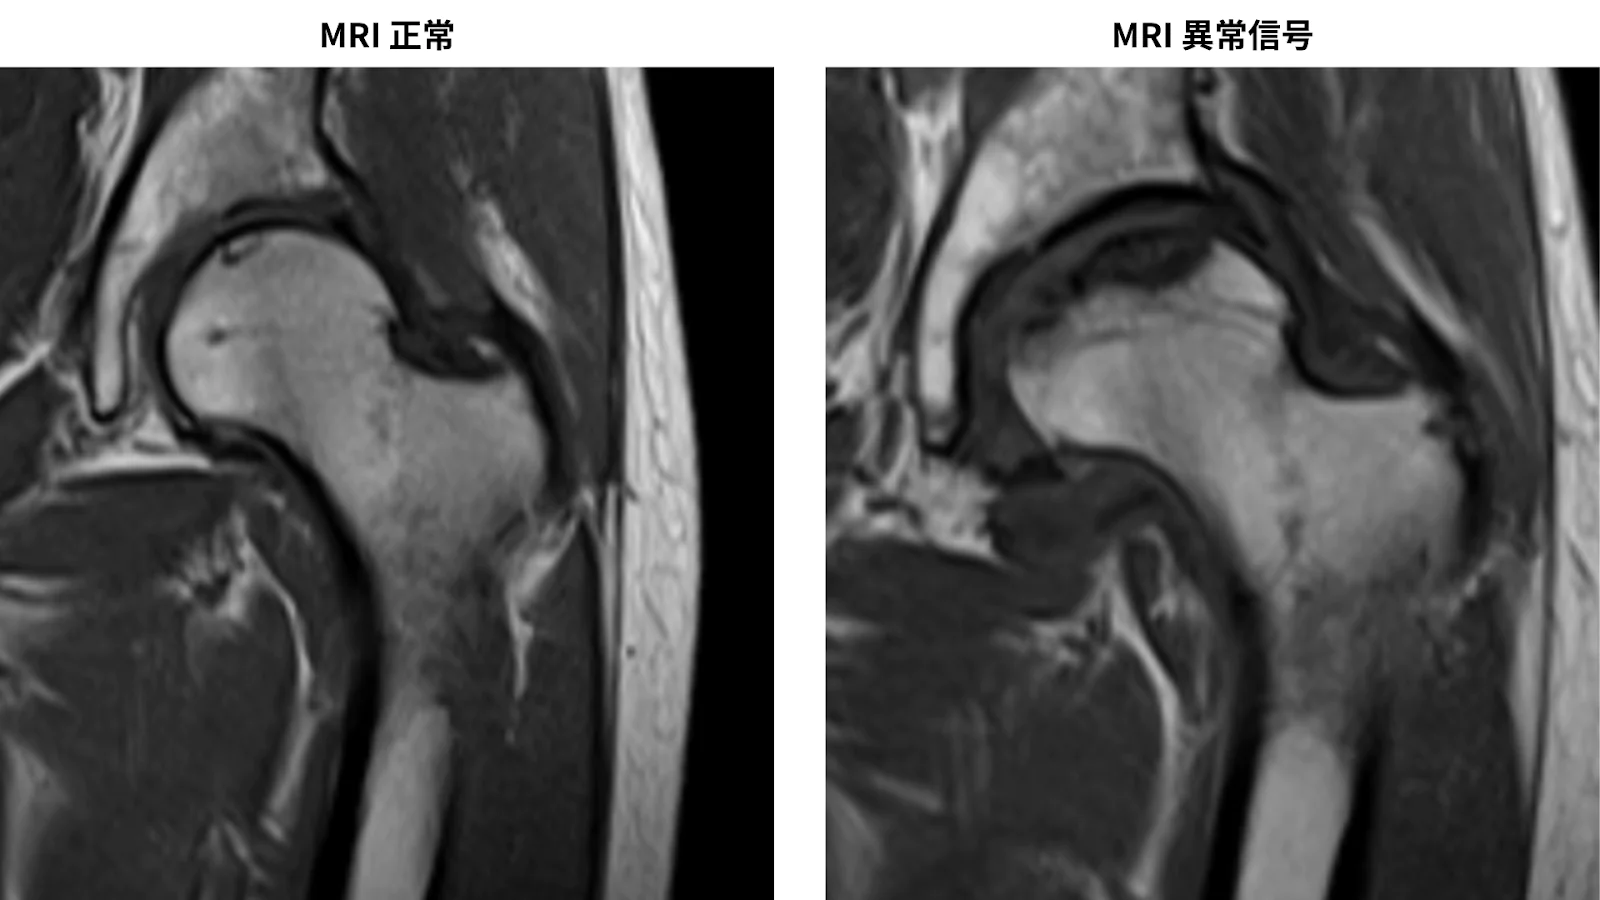

MRIやシンチグラム:

骨頭内の異常な信号域や「cold in hot」像を確認。